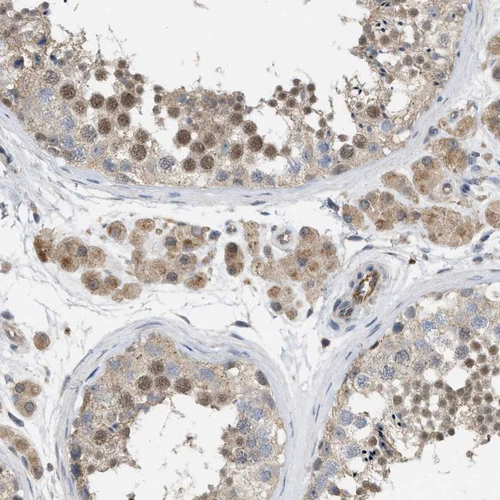

HPA019832

N-acyl phosphatidylethanolamine phospholipase D

Anti-NAPEPLD Antibody

Polyclonal Antibody against HUMAN NAPEPLD

Immunohistochemical staining of human cerebral cortex shows weak cytoplasmic positivity in neurons.